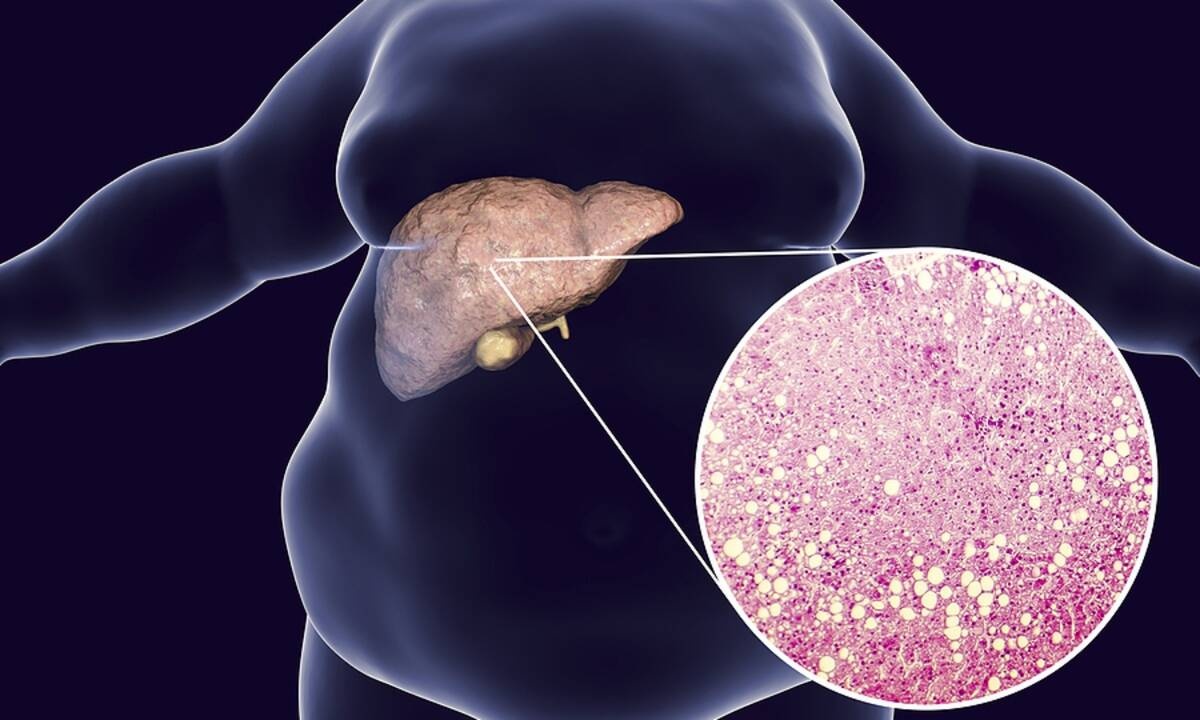

Λίπος στο συκώτι: Με ποιες τροφές θα το μειώσετε (εικόνες)

Το συκώτι είναι ένα από τα όργανα στα οποία το σώμα μας αποθηκεύει λίπος ώστε να δημιουργήσει «αποθήκες» ενέργειας.

Όταν όμως τα επίπεδα λίπους στο εσωτερικό του αυξάνονται υπερβολικά, τότε εκδηλώνεται η λεγόμενη λιπώδης νόσος του ήπατος.